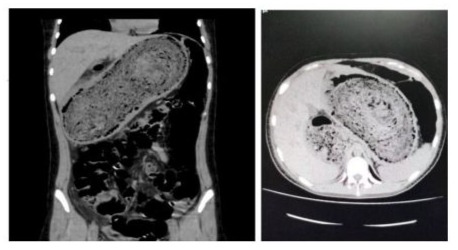

The patient underwent an abdominal Computed Tomography (CT) scan, which revealed a large, well-defined mass in the stomach, with an approximate diameter of 30 cm. The mass had a homogeneous density and showed no signs of necrosis or ulceration. The sagittal CT scan revealed dilation of the gastric chamber by a foreign body compatible with a bezoar [11,12]. Based on the CT scan results, it was decided to defer performing an endoscopy and proceed directly with surgical management.

Images (Tomografy)